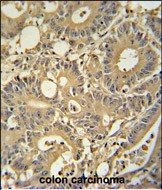

IHC 1/100-1/500 Human,Mouse,Rat

ImmunogenThis TPSD1 antibody is generated from rabbits immunized with a KLH conjugated synthetic peptide between 164-193 amino acids from the C-terminal region of human TPSD1.